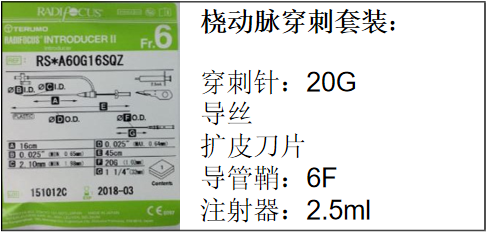

1.桡动脉鞘管

2%利多卡因,硝酸甘油注射液,1ml/2.5ml/10ml注射器,桡动脉鞘管套装,猪尾巴导管,SIM2导管,泥鳅导丝或0.35in交换导丝,桡动脉压迫止血器。